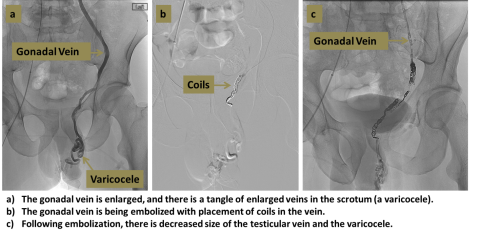

A varicocele is a dilated network of veins which occurs in the scrotum, usually on the left side, which can cause pain, swelling, and reduced fertility. Varicocele embolization is a minimally-invasive method of blocking these veins, which relieves these symptoms in a large proportion of patients.

An interventional radiologist uses ultrasound and X-rays to guide a catheter from the femoral vein in the groin into the gonadal vein (the source of the varicocele). Contrast injection is used to map the vein, and the vein is then occluded by using coils, sclerosants, or other agents.